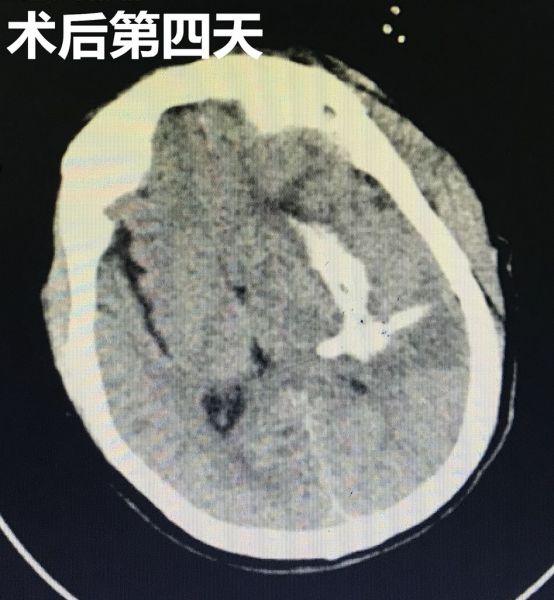

术后复查CT显示穿刺引流管位置良好。通过三天的引流血肿,再次复查CT显示颅内血肿已大部分清除,患者术前受压的脑组织也基本回位,病人的意识状态也比术前明显好转。目前患者病情稳定,正积极康复治疗中。

术后复查CT结果